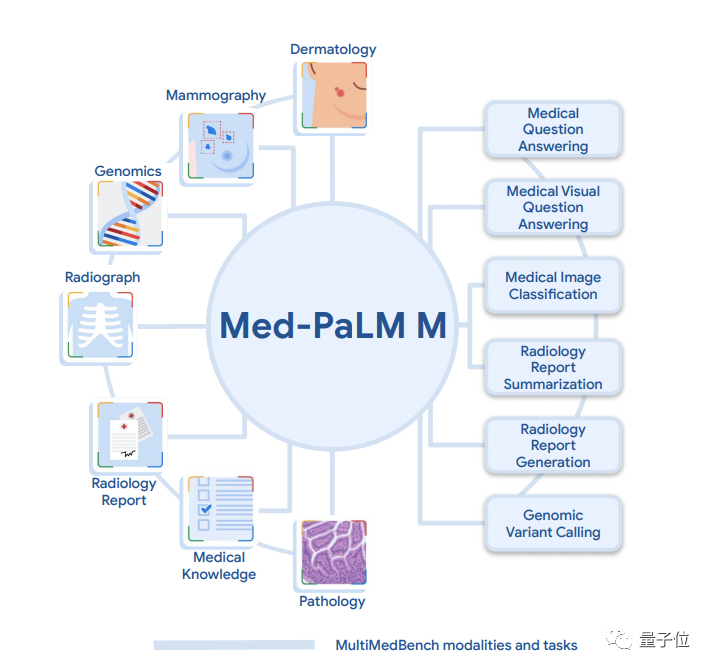

在正式了解Med-PaLM M之前,我们先简单介绍谷歌自建的多模态医学测试基准MultiMedBench。

谷歌表示,在MultiMedBench之前,市面上缺乏这样一个全面的多模态医学基准。

该基准由12个开源数据集和14个单独的任务组成,用于测量通用生物医学AI执行各种临床任务的能力。

其中12个数据集共包含了六种生物医学数据模式(文本、放射学(CT、MRI和X光)、病理学、皮肤病学、乳房X光检查和基因组学),14个任务则涵盖五种类型(问题回答、报告生成和摘要、视觉问题回答、医学图像分类和基因组变体调用)。

正如其名“M”代表多模态,Med-PaLM M相比之前谷歌发布的Med-PaLM、Med-PaLM-2等医疗大模型,是一个主打全科、通才的医疗AI,不仅能回答各种医学问题,还能直接看片、懂基因组学。